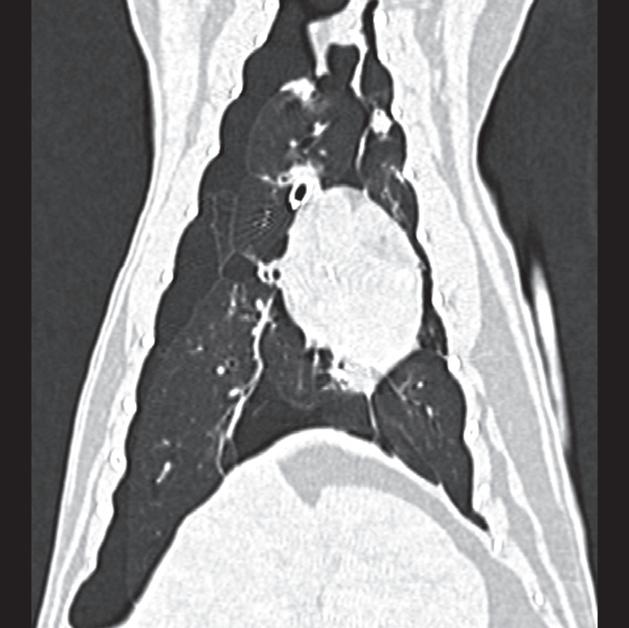

Badanie wykonano u 7-letniego rottweilera z rozpoznanym guzem nadnercza oraz nagłymi objawami dyskomfortu jamy brzusznej. Obrazy na ryc. a–c uporządkowano od strony doczaszkowej do doogonowej. Nadnercze prawe jest powiększone (a, d – otwarty grot strzałki) i ma widoczną ekscentryczną komponentę torbielowatą o densyjności płynu, która rozchodzi się doogonowo (a, b – strzałki). Tkanka miękka rozrostu oraz torebka nadnercza wykazują obwodowe wzmocnienie pokontrastowe. Torbielowata komponenta zmiany rozrostowej widoczna na obrazie odpowiada krwotokowi, który rozciąga się doogonowo w przestrzeni zaotrzewnowej (d). Dobrzusznie od zmiany widoczny jest moczowód (b – grot strzałki). Diagnoza makroskopowa i histologiczna została potwierdzona po chirurgicznym usunięciu zmiany (e – strzałka). Proszę zwrócić uwagę na porównanie obrazu TK zmiany (d) z wyciętym preparatem makroskopowym (f)